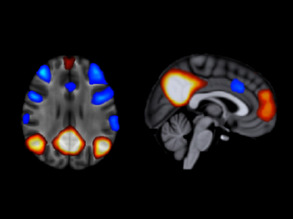

Dopamine Dip